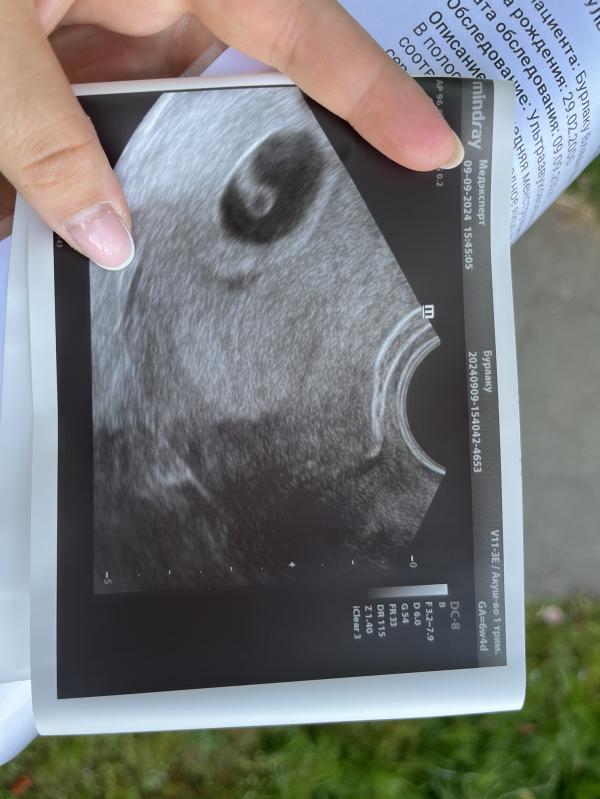

Узи на раннем сроке: что увидели? 09.09.2024, малыш здоров!

post image 1

Сделали узи ранней беременности!

09.09.2024

Мы здоровенькие❤️